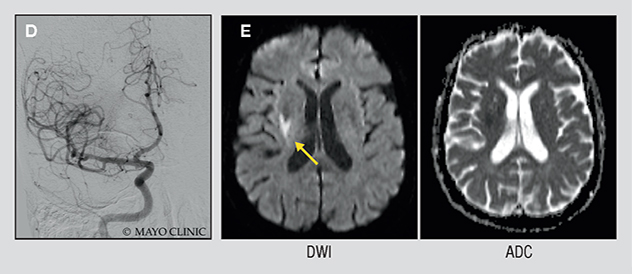

D. Angiogram after surgical removal of the clot shows normal blood flow. E. Diffusion-weighted imaging (left) and apparent diffusion coefficient mapping (right) done two days after the initial presentation show that the patient's stroke was very small. She experienced no clinical deficits.